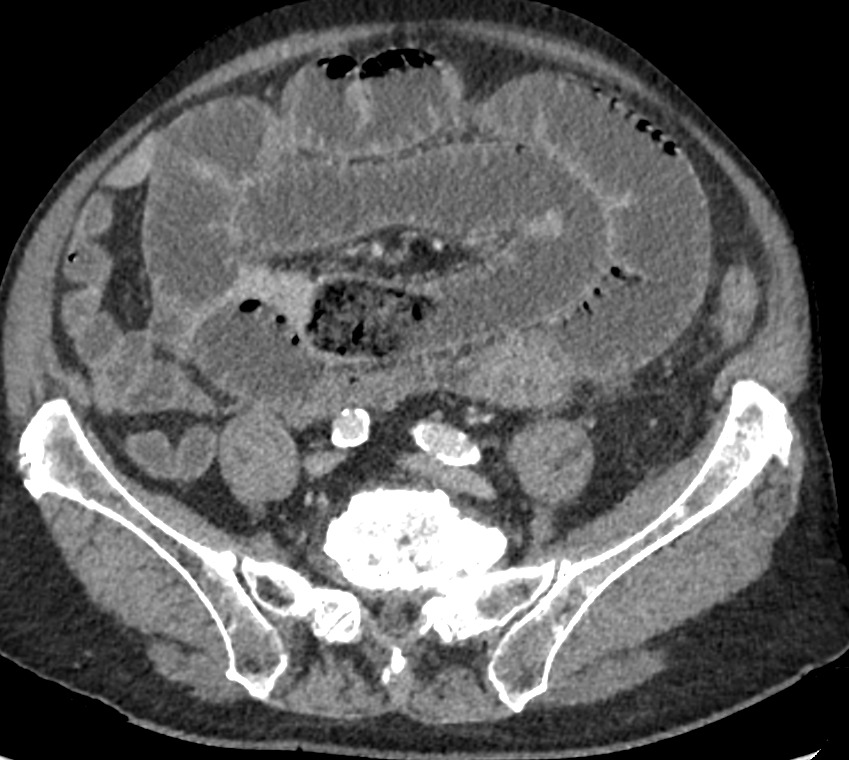

TC axial con contraste IV en fase portal.